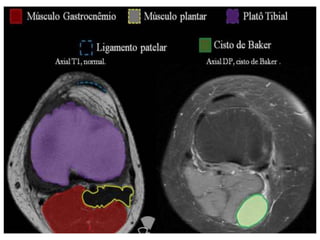

CASO CLÍNICO: CISTO DE BAKER

Caracteriza-se por uma hipertrofia (acúmulo de líquido)

da bolsa sinovial que separa o tendão da porção medial

do gastrocnênio do tendão semimembranoso. Causa:

atrito dos tendões.